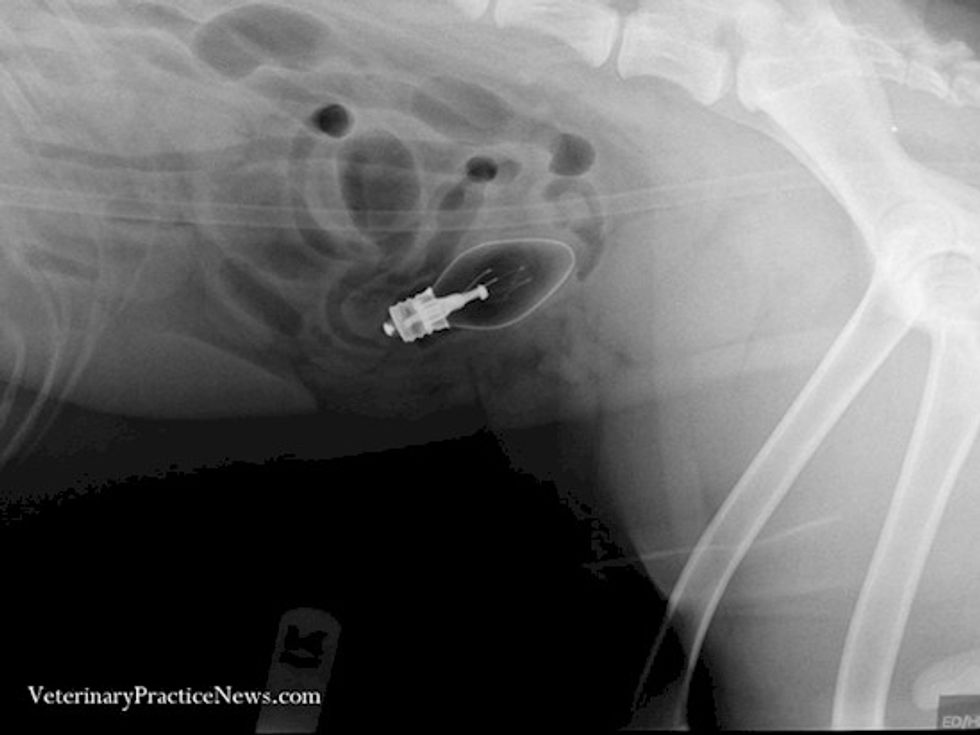

Kur një burrë kishte gjakderdhje, familjarët e dërguan shpejtë në urgjencë, që në fillim fajtori dukej të ishte një plagë nga një thikë. Por, kur mjekët e trajtuan plagën, ata kuptuan se gjakderdhja nuk po ndalej dhe se ajo vinte nga mbrapa.

Pasi e rrotulluan pacientin, ata zbuluan se sulmuesi i tij ia kishte futur një poç elektrik në anus, para se ta therrte me thikë. Ky është një objekt veçanërisht i vështirë për t’u hequr, dhe ai vdiq nga shoku septik pas procedurës.